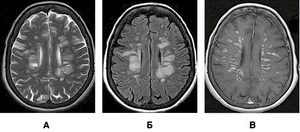

На рисунку 1 представлено МРТ-зображення головного мозку пацієнта з ГРЕМ у режимах Т2, Т2/Flair та Т1 із внутрішньовенним контрастуванням. Зокрема, візуалізуються двобічні вогнища округлої та овоїдної форми, гіперінтенсивні в режимах Т2 та Т2/Flair, які в більшості випадків накопичують контраст.

/images/nn257-1622023r1_.jpg)